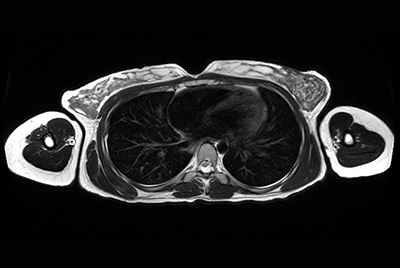

Chest overview

Chest imaging